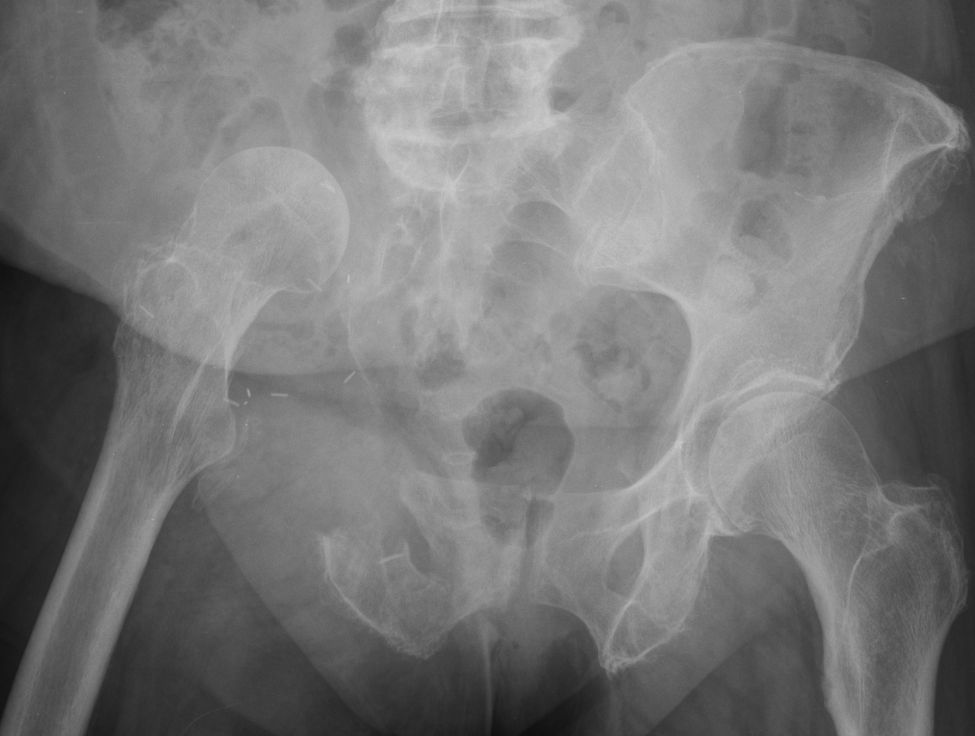

Röntgenbild nach radikaler Hemipelvektomie.![]() |